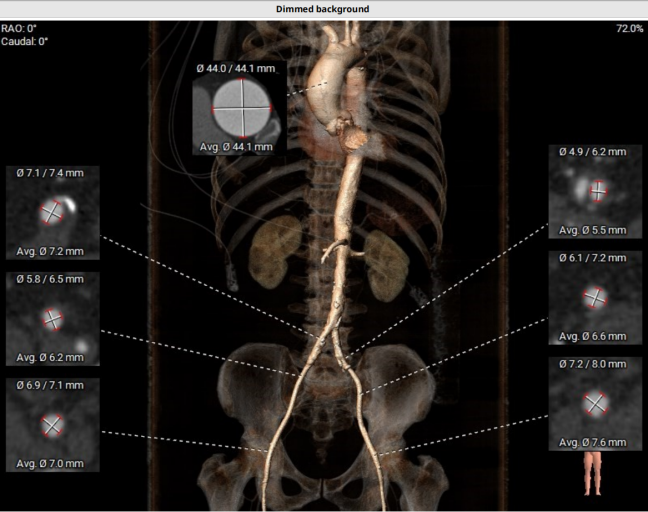

术前CT提示

血管入路评估:左骼总可见顺向夹层;